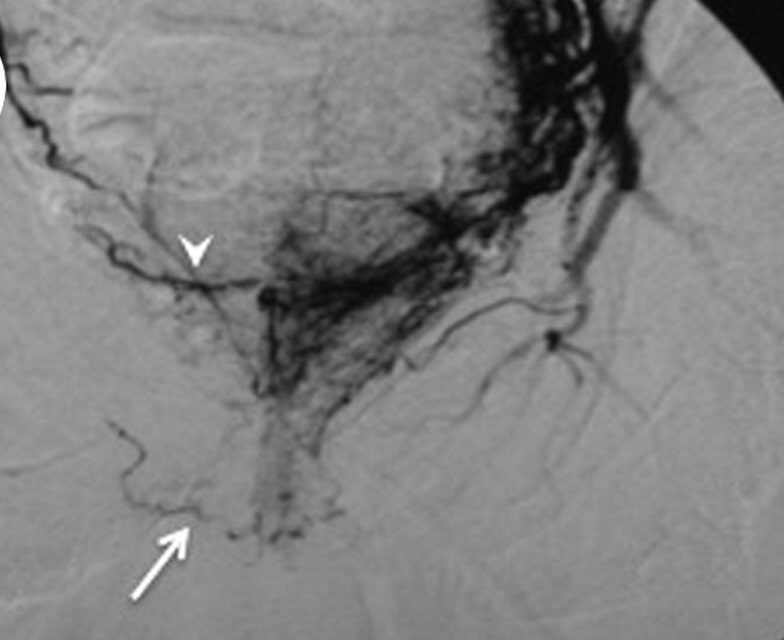

前列腺血管解剖 前列腺是双重动脉血管供应器官。其血管分为前侧前列腺动脉和尾侧前列腺动脉【2】。前侧动脉主要供应中央腺体和前列腺增生的结节,为手术时主要栓塞的动脉。尾侧动脉主要供应外围和尾部的腺体。两支动脉为共干情况的为60%,各自起源的为40%。进行前列腺动脉栓塞最关键的是识别前列腺动脉。前列腺动脉解剖的知识对于正确地选择性前列腺动脉导管术非常重要。在进行动脉治疗之前,有些是必须的: 1. 发现前列腺动脉; 2. 前列腺动脉的开口; 3. 方向 4. 不同的前列腺动脉分支 5. 与周围动脉的吻合 最常见的动脉供血(41.5%-74.3%)1. 要么直接从阴部内动脉(internal pudendal artery)发出;2. 要么通过起源于膀胱下动脉(inferior vesical artery)的膀胱前列腺干(vesico-prostatic trunk)和前列腺动脉。 CTA 对于前列腺动脉选择性插管非常重要【1】,这是因为CTA可以发现: 1. 正常解剖;2. 血管迂曲性;3. 血管阻塞;4. 解剖变异。

Pelvic DSA with selective catheterization of the internal iliac arteries and 3D VR【1】

高元安【3】、李光忠【4】在国内期刊发表关于前列腺动脉解剖的影像学和解剖学数据。彼此之间不尽相同,而且和国外文献差距也较大。 小结: 前列腺动脉的开口,方向和吻合是血管内治疗前必需知道的。 AngioCT有助于发现前列腺动脉的变异和指导选择性血管造影 DSA 可以较好地证实对栓塞不利的动脉吻合 1. Bilhim T, Pisco JM, Furtado A, Casal D, Pais D, Pinheiro LC, O'Neill JE. Prostatic arterial supply: demonstration by multirow detector angio CT and catheter angiography. Eur Radiol. 2011 May;21(5):1119-26. doi: 10.1007/s00330-010-2015-0. Epub 2010 Nov 30. 2. Bilhim T, Tinto HR, Fernandes L, Martins Pisco J. Radiological anatomy of prostatic arteries. Tech Vasc Interv Radiol. 2012 Dec;15(4):276-85. doi: 10.1053/j.tvir.2012.09.006.